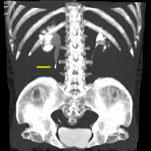

问题 男,36岁,反复发作的右侧腰背部疼痛伴血尿1年余,CT如图所示,下列说法正确的是 ( )

选项 A、右输尿管结石 B、右输尿管上段钙化 C、右输尿管上段扩张 D、右输尿管内可见沿输尿管走行的高密度影 E、右侧肾盂肾盏扩张

答案 ACDE